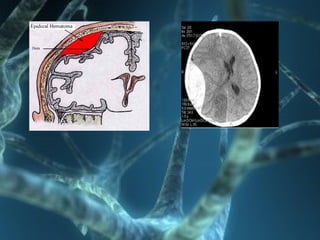

Epidural Hematomas (EDH) •Peak incidence in 2nd decade • Source  meningeal vessel, Dural venous sinus, diploic vein from skull fracture • History of minor head injury with fall • Clinical presentaion  wrt size, location, rate of accumulation – Lucid interval (33%), non specific – Confusion, lethargy, agitation, focal neurological deficits.

Diagnosis • CT isdiagnostic • Initial Ct Hyperdense collection beneath skull • Actively bleeding- Mixed densities